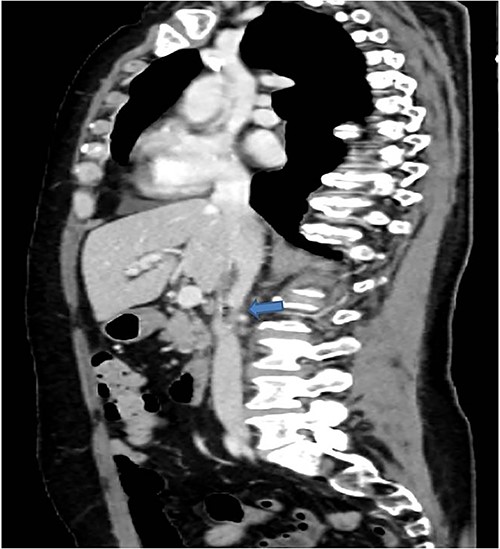

A 58-years-old woman arrived to our emergency department for fever (39.5°C) with chills and diffuse abdominal pain radiating to the back about 2 weeks. Her medical history included a hysteroannexectomy with sigmoid resection for an ovarian tumor that occurred 2 years earlier (Stage IIb) and adjuvant radiotherapy and traditional chemotherapy, subsequently followed by biological therapy with bevacizumab completed 6 months earlier. The patient was currently disease free and in follow-up. On admission, laboratory test showed a white cell count of 18 700 mL and microcytic anemia (hemoglobin level, 6.6 g/dL) with an increase in inflammation indices (CRP 26.2 mg/dl). Evidence of several digestive tract bacteria, including Enterococcus faecium, Escherichia coli and Weissella confusa, was disclosed by means of several hemocultures. A specific antibiotic therapy was started and blood transfusions were performed for the anemia found. Therefore, the patient underwent a chest and abdomen CT scan, which showed the presence of strong adherence between the IVC at the origin of the left renal vein and the third duodenal portion with air inside the vena cava and thrombotic-like hypodense material as for a DCF (Figs 1 and 2).

CT scan showed the presence of strong adherence between the IVC at the origin of the left renal vein and the third duodenal portion.

In coronal view the arrow points the air inside the vena cava and thrombotic-like hypodense material.